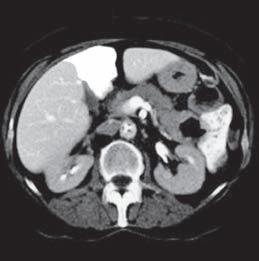

Kazuistika I (segmenty jaterní tkáně)